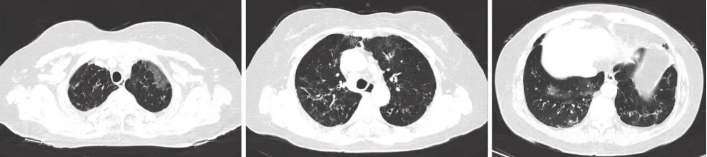

患者女性,66岁,因“咳嗽咳痰4年余,加重半年”入院。患者4年余前无明显诱因出现咳嗽、咳白痰,无胸闷气喘,季节交替时症状明显,受凉后加重,静脉用抗炎药后症状可缓解(具体不详)。近半年患者上述症状加重、痰转为黄色黏痰,量多。2024-05-04及2024-05-26于当地两家医院分别行胸部CT,均提示两肺纹理紊乱模糊,肺野透亮度增高,两肺斑片状、索条状高密度影,边缘模糊,支气管壁增厚,左肺下叶囊状透亮影,两肺门结构未见明显异常,气管、支气管通畅,纵隔内未见明显肿大淋巴结,两侧胸腔少量积液。双侧胸膜局部增厚。静脉予以红霉素、头孢菌素抗炎症状稍好转。1周前患者受凉后再发咳嗽咳痰,咳黄痰,伴活动后胸闷气喘,门诊查多排CT胸部平扫(图1):两肺间质性炎症;两肺支气管扩张;纵隔淋巴结稍大;两侧胸膜增厚;脂肪肝;肝囊肿可能。予以金荞麦片、头孢呋辛酯、左氧氟沙星等处理。现患者为寻求进一步诊治,收入我科。

图1 患者2024年7月胸部CT像

两肺见斑片状、索条状高密度影,部分周围见囊状、柱状支气管影;纵隔淋巴结稍大;两侧胸膜增厚。